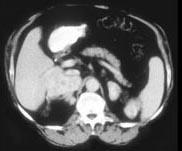

问题 女,32岁,阵发性高血压2年余,请结合所提供图像,作出诊断 ( )

选项 A、左肾上腺嗜铬细胞瘤 B、左肾上腺淋巴瘤 C、左肾上腺腺癌 D、左肾上腺转移瘤 E、左肾上腺腺瘤

答案 A